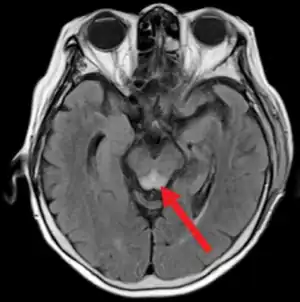

- Wernicke's encephalopathy: Arising from thiamine (B1) deficiency, usually in the setting of alcoholism.